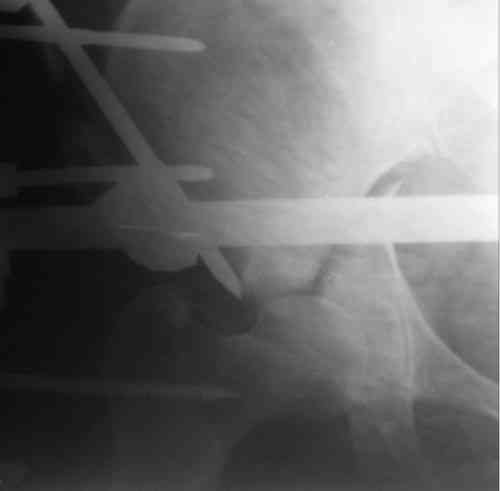

Пациентка 38 лет. В результате ДТП 02.09.06 получила поперечный перелом правой вертлужной впадины, центральный вывих правого бедра, разрыв правого крестцово-подвздошного сустава.

В одной из районных больниц вывих устранен, наложена система вытяжения по оси бедра и за вертельную область. Спустя 2 недели выполнен ВЧКО модулем "таз-бедро". Учитывая возраст пациентки и остаточный диастаз в области свода вертлужной впадины предполагается демонтаж аппарата, открытая репозиция и внутренний МОС вертлужной впадины через внутритазовый доступ.

На показанных снимках повреждение правого КПС не очень заметно...

У меня создалось впечатление( одна из РГ), что участок суставной поверхности нагрузочной зоны вертлужной впадины вдавлен( постарайтесь сделать КТ). Если это подтвердиться, то из внутритазового доступа отрепонировать будет невозможно.

Чтобы уменьшить риск инфекции после открытой репозиции перед основным вмешательством неплохо было бы дождаться полного заживления стержневых

проколов.